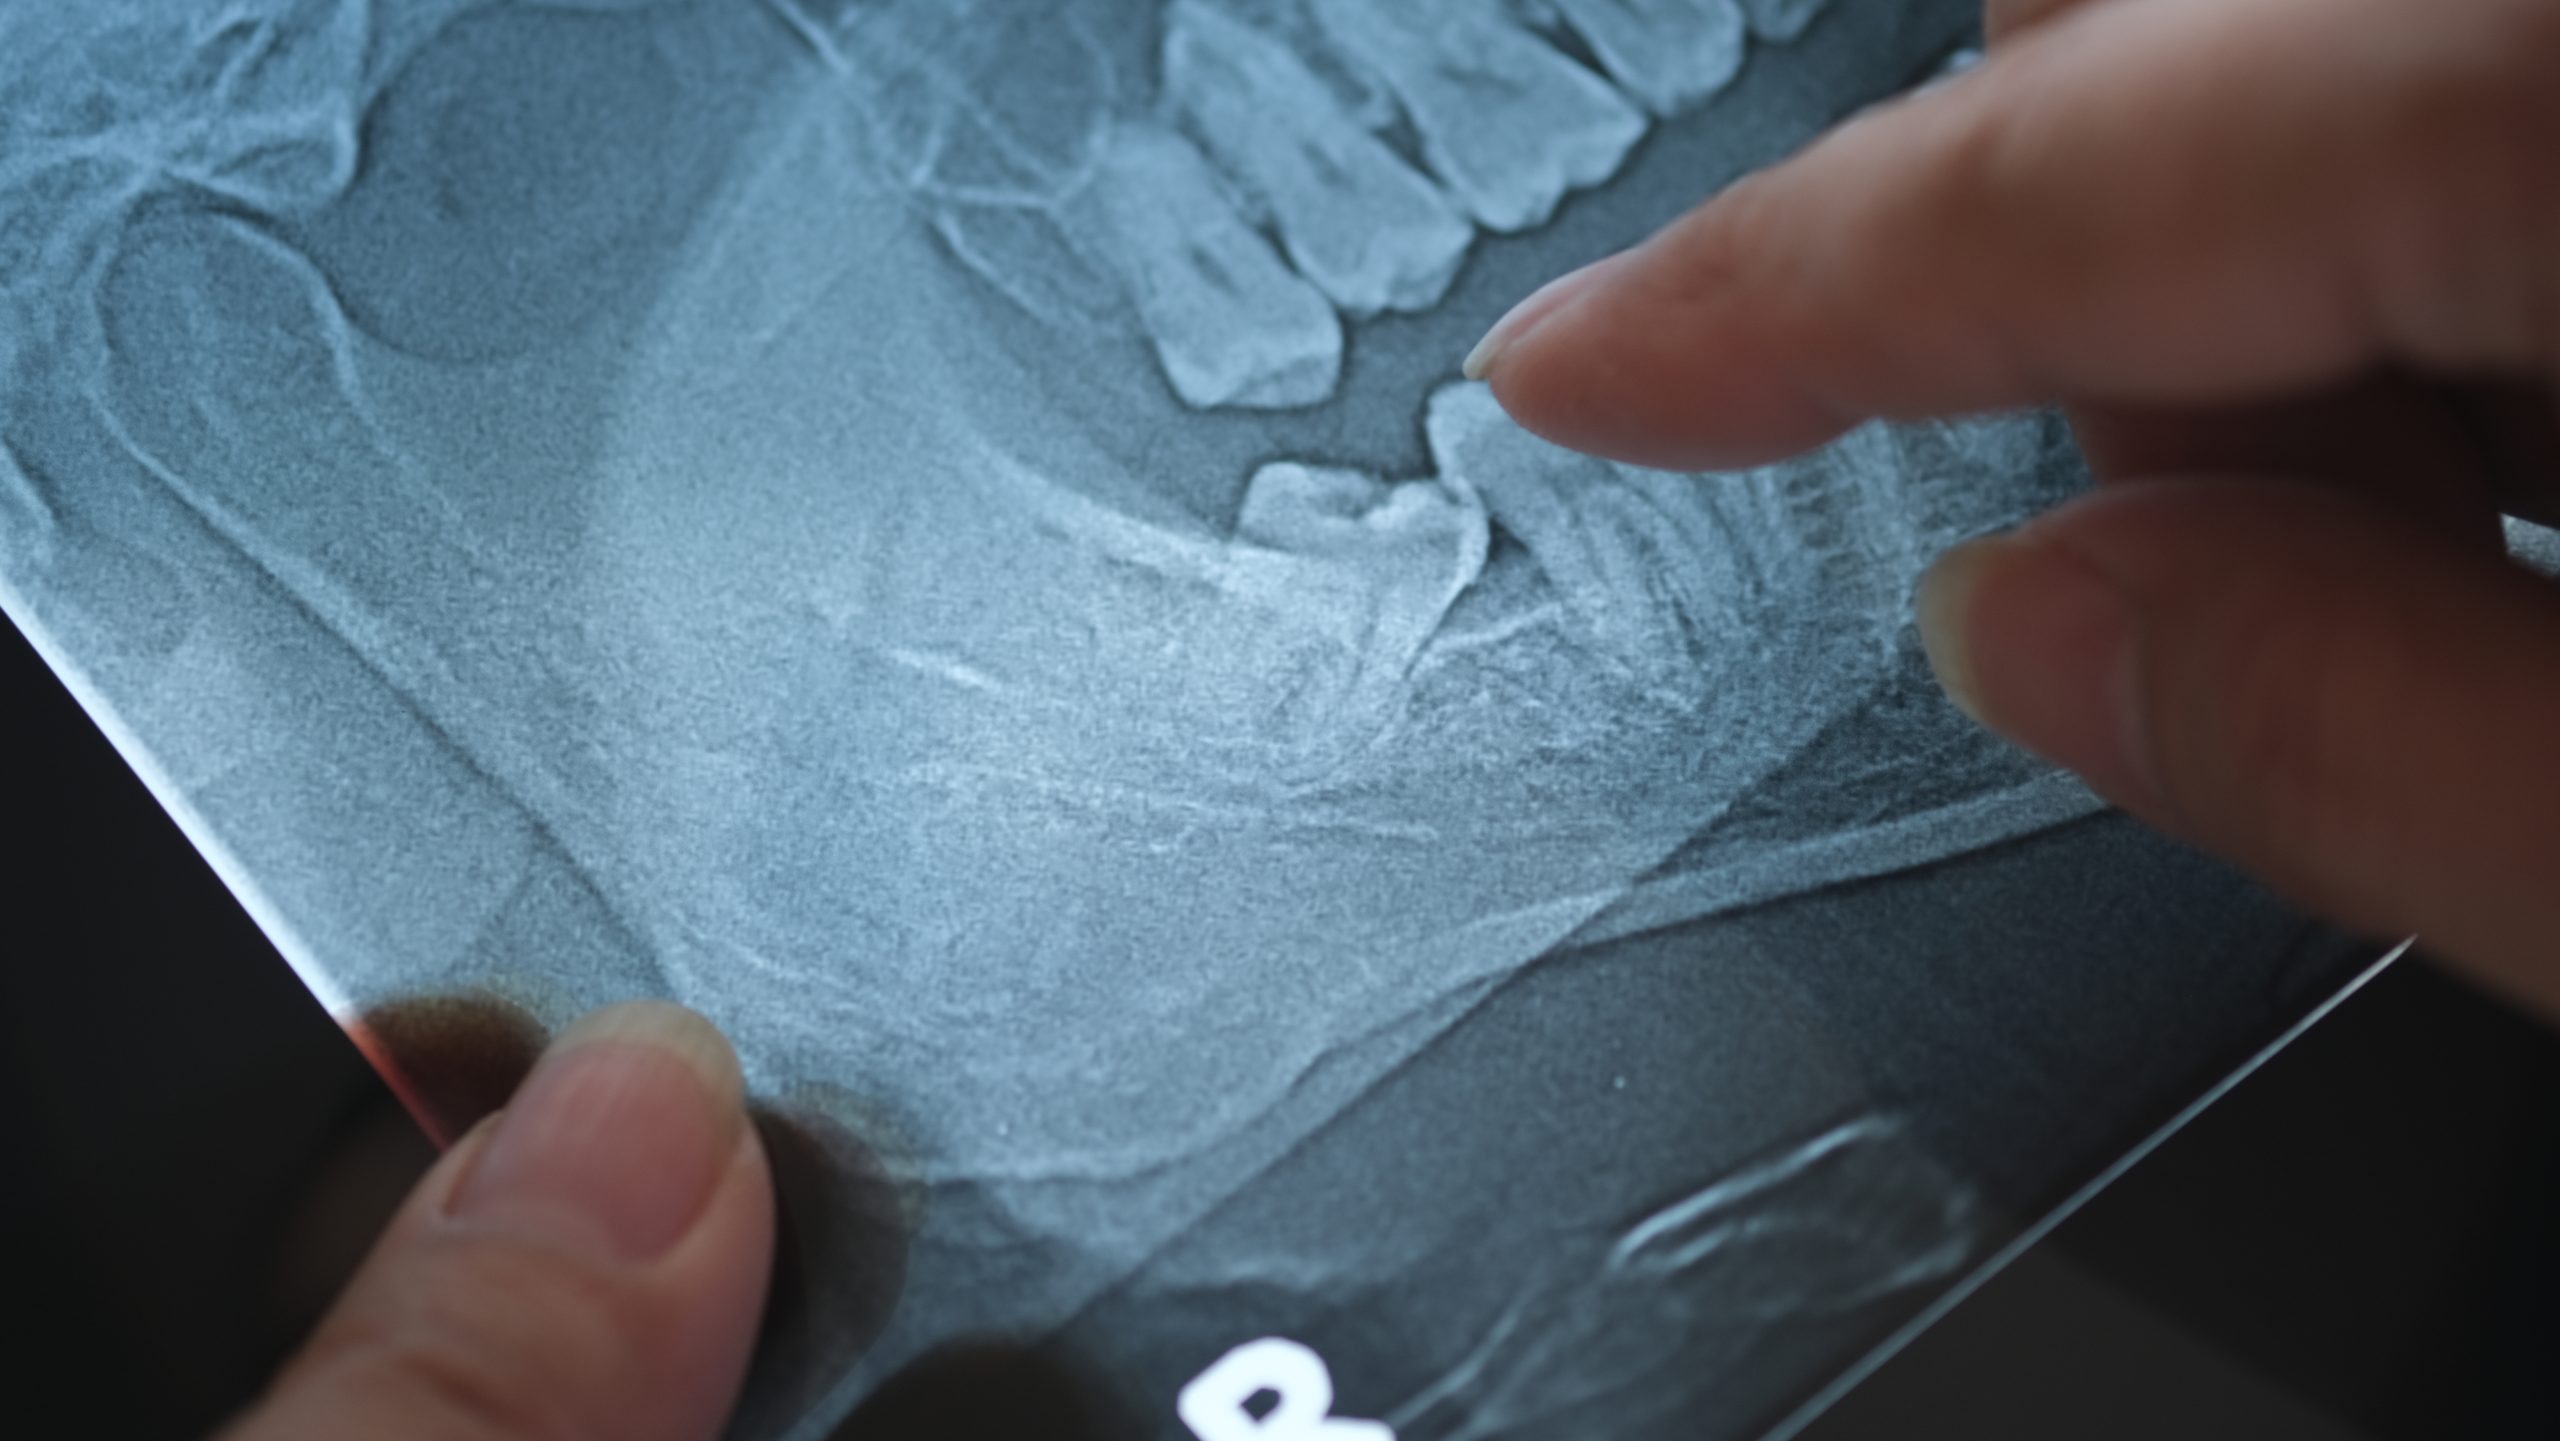

We perform a detailed oral exam, digital X-rays, and CBCT imaging to assess tooth position and complexity.

CBCT imaging allows accurate evaluation and helps determine the safest treatment method.